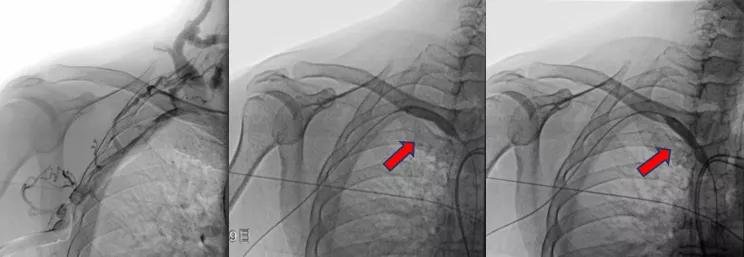

病变明确了,张主任当机立断,立即进行介入手术。张东亮主任医师与付晨主治医师在新建成的新龙泽院区介入手术中心进行了局麻下经皮穿刺血管内介入治疗。张主任凭借丰富的经验、娴熟的手法很快将超滑导丝通过病变部位,10mm高压球囊将狭窄部位扩张至无回弹,再次造影确认,心细的张主任又发现了新的端倪——近心端静脉还有一处狭窄!此前这一病变在CTA+CTV结果中并没有发现,张主任毫不犹豫,球囊再前进50mm、*压打**扩张,再次造影复测,血流通畅、侧支循环和返流消失。

狭窄的两处病变静脉在球囊的逐渐加压得以重新开通